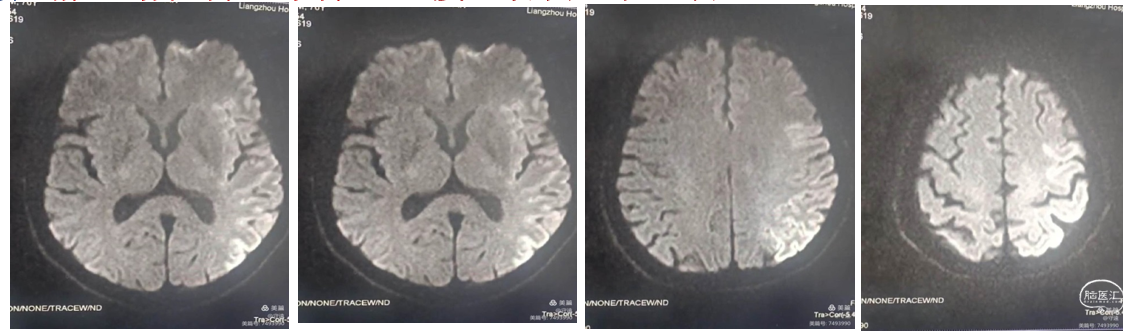

患者男性,70岁,突发意识模糊,右侧肢体失动2小时,NiHss评分20分,房颤,CT检查:无出血和脑沟回的肿胀。MR检查DwI显示:左侧大脑中动脉浅淡高密度影。DWI-ASPECT评分6分。诊断:急性脑梗塞:心源性栓塞可能性大。

评估符合三个6的原则:时间窗<6小时、 NiHss评分>6分,CT-ASPECT评分10分。考虑静脉溶栓再通率低,直接血管内取栓治疗。

局麻下行血管内治疗:行右侧股动脉穿刺,脑血管造影真实左侧大脑中动脉M1段闭塞。血管断面呈“刀切征”or“截断征”。大脑前动脉部分代偿。

手术过程:银蛇070中间导管到达M1段直接抽吸。

裸奔:由于颈内血管路途迂曲不明显,路图下银蛇070中间导管“裸奔”到达M1段接触血栓部位。

踹马桶抽吸: “猛抽”将血栓吸入导管,进行快速踹、踹、踹马桶,注射器无回血,边踹负压抽吸,撤出体外,检查中间导管和注射器抽出2块红色血栓,冒烟观察血管再通。

抗血小板聚集:再次将微导管置于M1段起始部,给予替罗非班8mL,1mL/min推注。造影显示远端血流通畅。

术后24小时复查CT,无出血,脑中线无移位,左侧基节区轻度水肿。意识清,右下肢肌力3级。术后抗血小板聚集:术后24小时给予阿司匹林100mg、氯吡格雷75mg、阿托伐他汀钙片40mg。术后4天,复查CT示:额颞部小面积低密度梗死区,左侧大脑半

球轻度水肿。